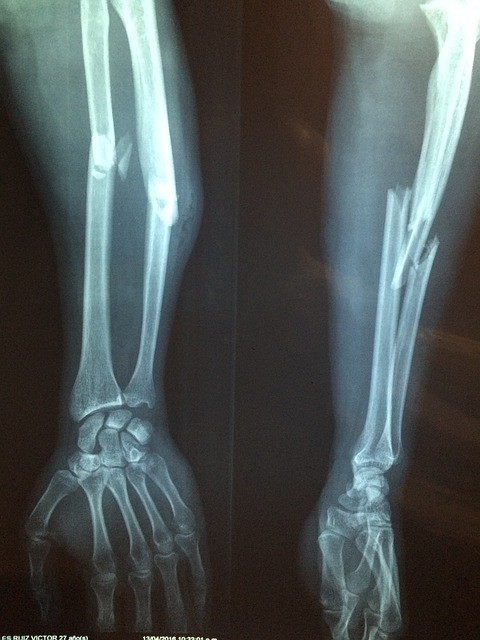

Loss of bone strength is a notably bad development for people with seizures. This is because epileptics often flail uncontrollably, hit things, and fall down. Any of these activities may greatly increase the risk of fracture.